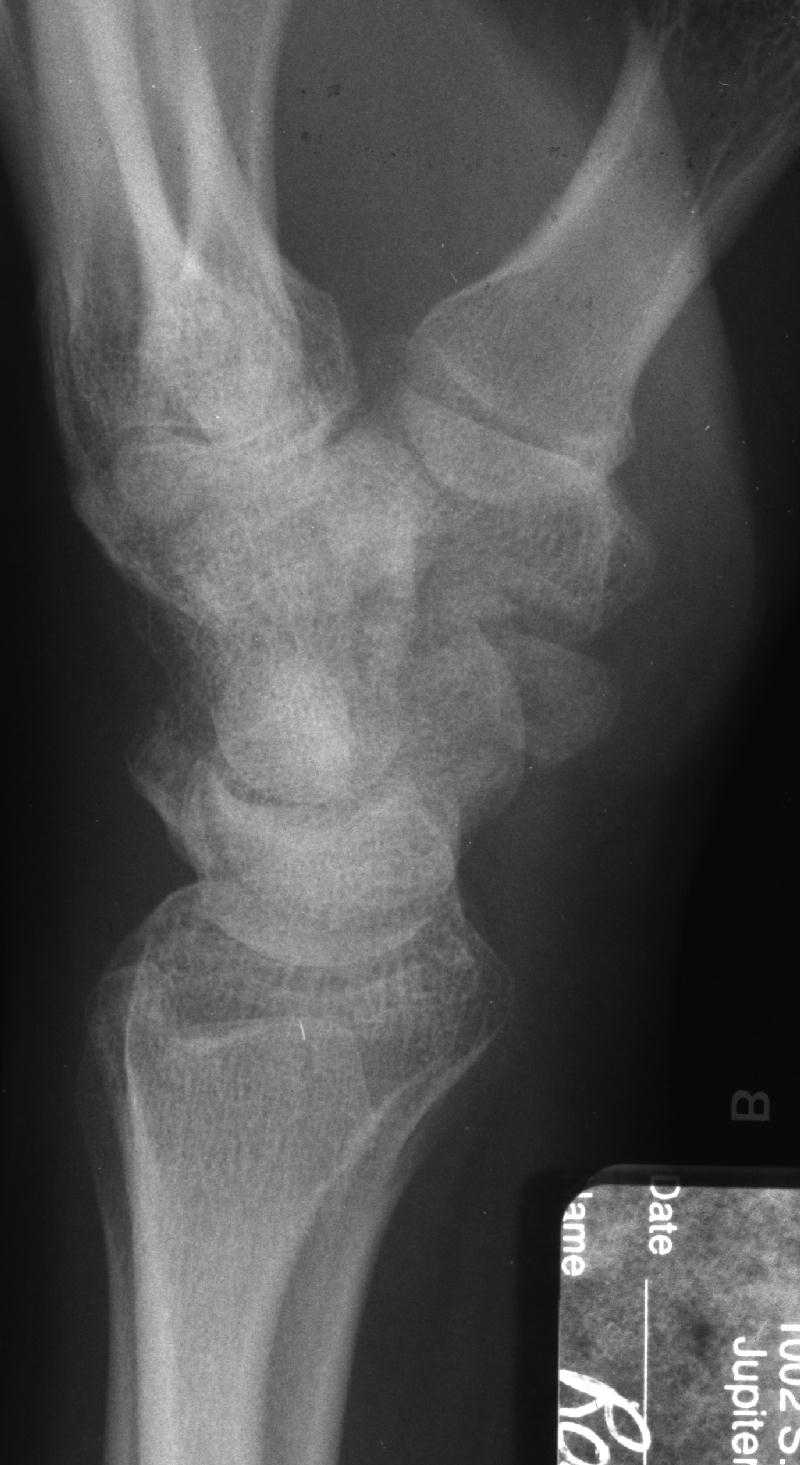

Clinical Example: Scaphoid Tubercle Fracture

scaphoid tubercle fracture